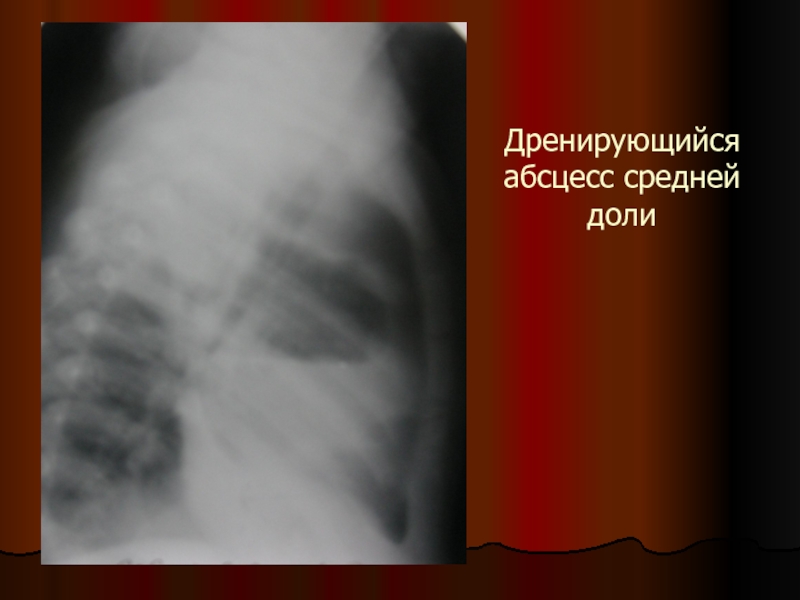

Слайд 28Дренирующийся абсцесс средней доли